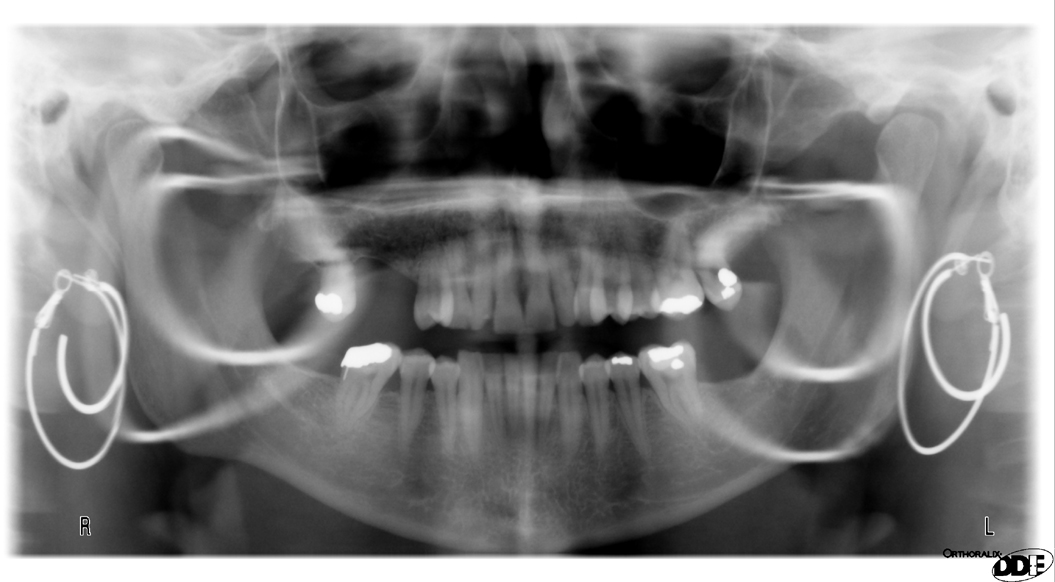

got my first xray with all my piercings in taken at the orthodontist Nose Ring Dental X Ray However its up to the clinician to. As for record keeping, a dentist may. Contact us for costs and all types of x. For extra oral they ideally should be taken out but. For intra oral ones then they can be left in. The nose ring will appear on the xray in an area that can block a possible tooth. Nose Ring Dental X Ray.

The way my nose ring and lip ring show up in my dental Xrays r Nose Ring Dental X Ray For intra oral ones then they can be left in. However its up to the clinician to. The nose ring will appear on the xray in an area that can block a possible tooth image. As for record keeping, a dentist may. For extra oral they ideally should be taken out but. Contact us for costs and all types of. Nose Ring Dental X Ray.